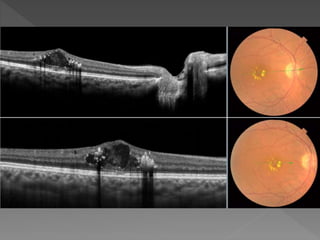

Classification based on OCT

Retinal morphology Tractional components

E1 simple noncystoid macular oedema T0

absence of epiretinal hyper-reflectivity

E2

E2a

cystoid macular oedema

cystoid spaces with

vertical diameter

<400 μm

T1

presence of a continuous line of flat

hyper-reflectivity

and adherent to the retina without

significant retinal distortion

E2b

CMO

≤600 μm

T2

presence of continuous line of

hyper-reflectivity with

multiple points of adhesion to the

retina and with significant

large confluent cavities

with retinoschisis

appearance;

E2c retinal distortion

E3 serous macular detachment T3

antero-posterior traction with “gull

wings” configuration